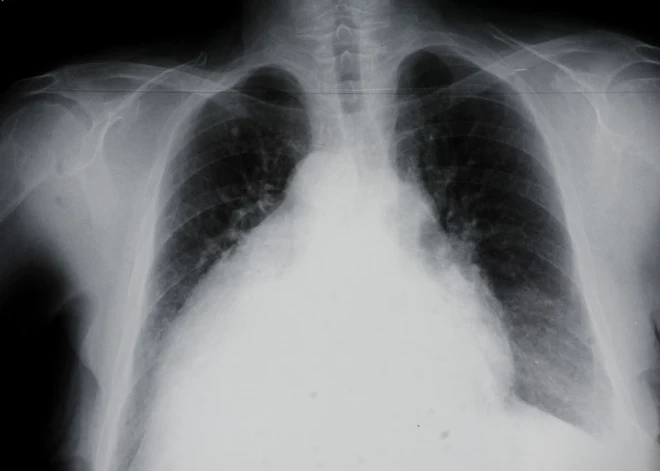

Plaušu vēzis ir stāvoklis, kad plaušās notiek patoloģiska vai neparasta šūnu augšana. Saskaņā ar PVO datiem plaušu vēzis veido aptuveni 13% no visiem vēža gadījumiem pasaulē. Tā kā plaušas ir cilvēka ķermeņa elpošanas mehānisma galvenais orgāns, daudzi domā, ka akūtas elpošanas problēmas vai sāpes ķermeņa augšdaļā ir vienīgās šīs slimības pazīmes. Tomēr tas tā nav.

Kāpēc diagnostika nav vienkārša?

Plaušu vēža daba ir tāda, ka vairumā gadījumu pacientam nav nekādu agrīnu specifisku simptomu, un parasts rentgena izmeklējums, kā skrīninga metode, nav efektīvs. Un pat ja simptomi ir, tad tie nav specifiski un var “maskēties” zem citu plaušu slimību izpausmēm, piemēram, hroniskas obstruktīvas plaušu slimības, pneimonijas vai dažādu plaušu infekciju simptomiem. Arī Covid-19 infekcijas ietekmē pacientiem bieži tiek skartas plaušas, un ne vienmēr var izvērtēt vai tās ir tikai sekas pēc Covid-19 izslimošanas, jo arī audzējs var izskatīties līdzīgi.